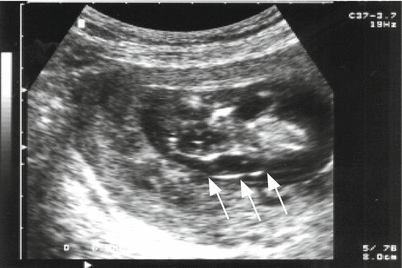

Fig. 13.10

Cross-section of a 13-week fetal head, normal karyotype, and increased fluid in the neck region (arrows)